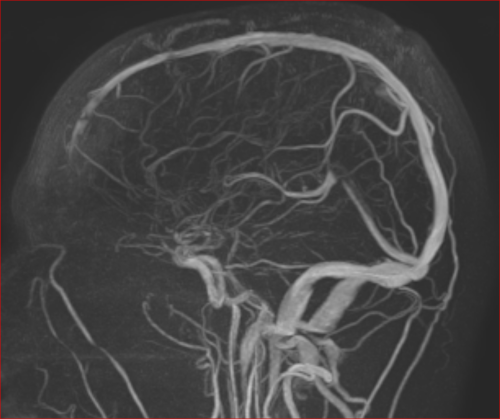

Aneurysma re. 7 mm Darstellung in einer DSA (digitalen Subtraktionsangiographie) links nur ein 2 mm „Baby-Aneurysma“ Im MRT war zuvor das linke Aneurysma aufgefallen, die Auflösung einer DSA ist technisch im MRT nicht erzielbar, beide A. liegen in der ACM Bifurkation jeweils, das re. Aneurysma wurde erfolgreich operiert, das linke Aneurysma wird kontrolliert.